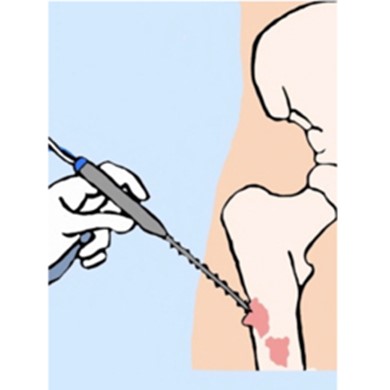

This is a procedure that involves removing a tumor (malignant or benign) of the soft tissues (muscle or fat) while preserving the surrounding healthy bone and soft tissues.